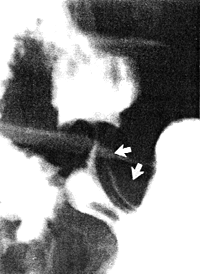

After a variable interval peristaltic contractions commenced in the gastric corpus in all cases. These narrow, annular waves were seen to proceed along the body of the stomach in a caudal direction as far as a point 3.0 to 4.0 cm proximal to the pyloric aperture. At this point each caudally travelling peristaltic wave came to a halt, i.e. it failed to advance any further, and ended in a concentric or cylindrical contraction of the entire distal 3.0 to 4.0 cm of the stomach (Fig. 13.6).

![]() |

| Fig. 13.6. Point at which peristaltic wave stops (curved arrows). Pyloric aperture (straight arrow). The region between the curved and straight arrows is distal 3-4 cm of stomach. |

A caudally travelling peristaltic wave was never seen to proceed as far as the pyloric aperture.